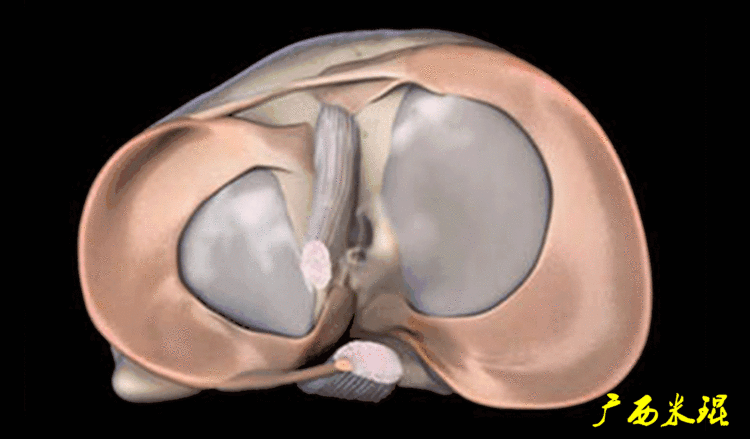

二、半月板损伤MR诊断的陷阱1:裙边样半月板(1)正常半月板的裙边正常半月板体部的游离缘有时候可以“变形”呈“裙边样或荷叶边样”,MR以及关节镜手术中都能够见到,特别是内侧,可能与内侧半月板游离缘更菲薄,而滑膜缘又被半月板胫骨韧带牢靠固定有关,这种改变可以通过改变膝关节的屈伸状态而消失。

有时候我们在MR上看见内侧半月板信号正常,半月板体部呈单裙边改变,周围软骨正常。

有时候半月板体部呈双裙边改变,周围软骨正常,以上这样的情况半月板都是正常的,不是损伤。

(2)退变撕裂半月板的裙边并不是所有的裙边都是正常的,下面这张冠状位MR,膝关节内侧间室软骨磨损严重,半月板与股骨髁以及胫骨平台的对合都不正常,半月板信号异常,形态裙边状,这种情况下的半月板一般都有损伤。

(3)半月板缝合后的裙边如果病人有半月板缝合的手术史,特别是较长的纵裂以及桶炳状撕裂的缝合,由于半月板对合不够整齐、或者缝合的松紧度不一致等等原因,术后也常常可以见到裙边。